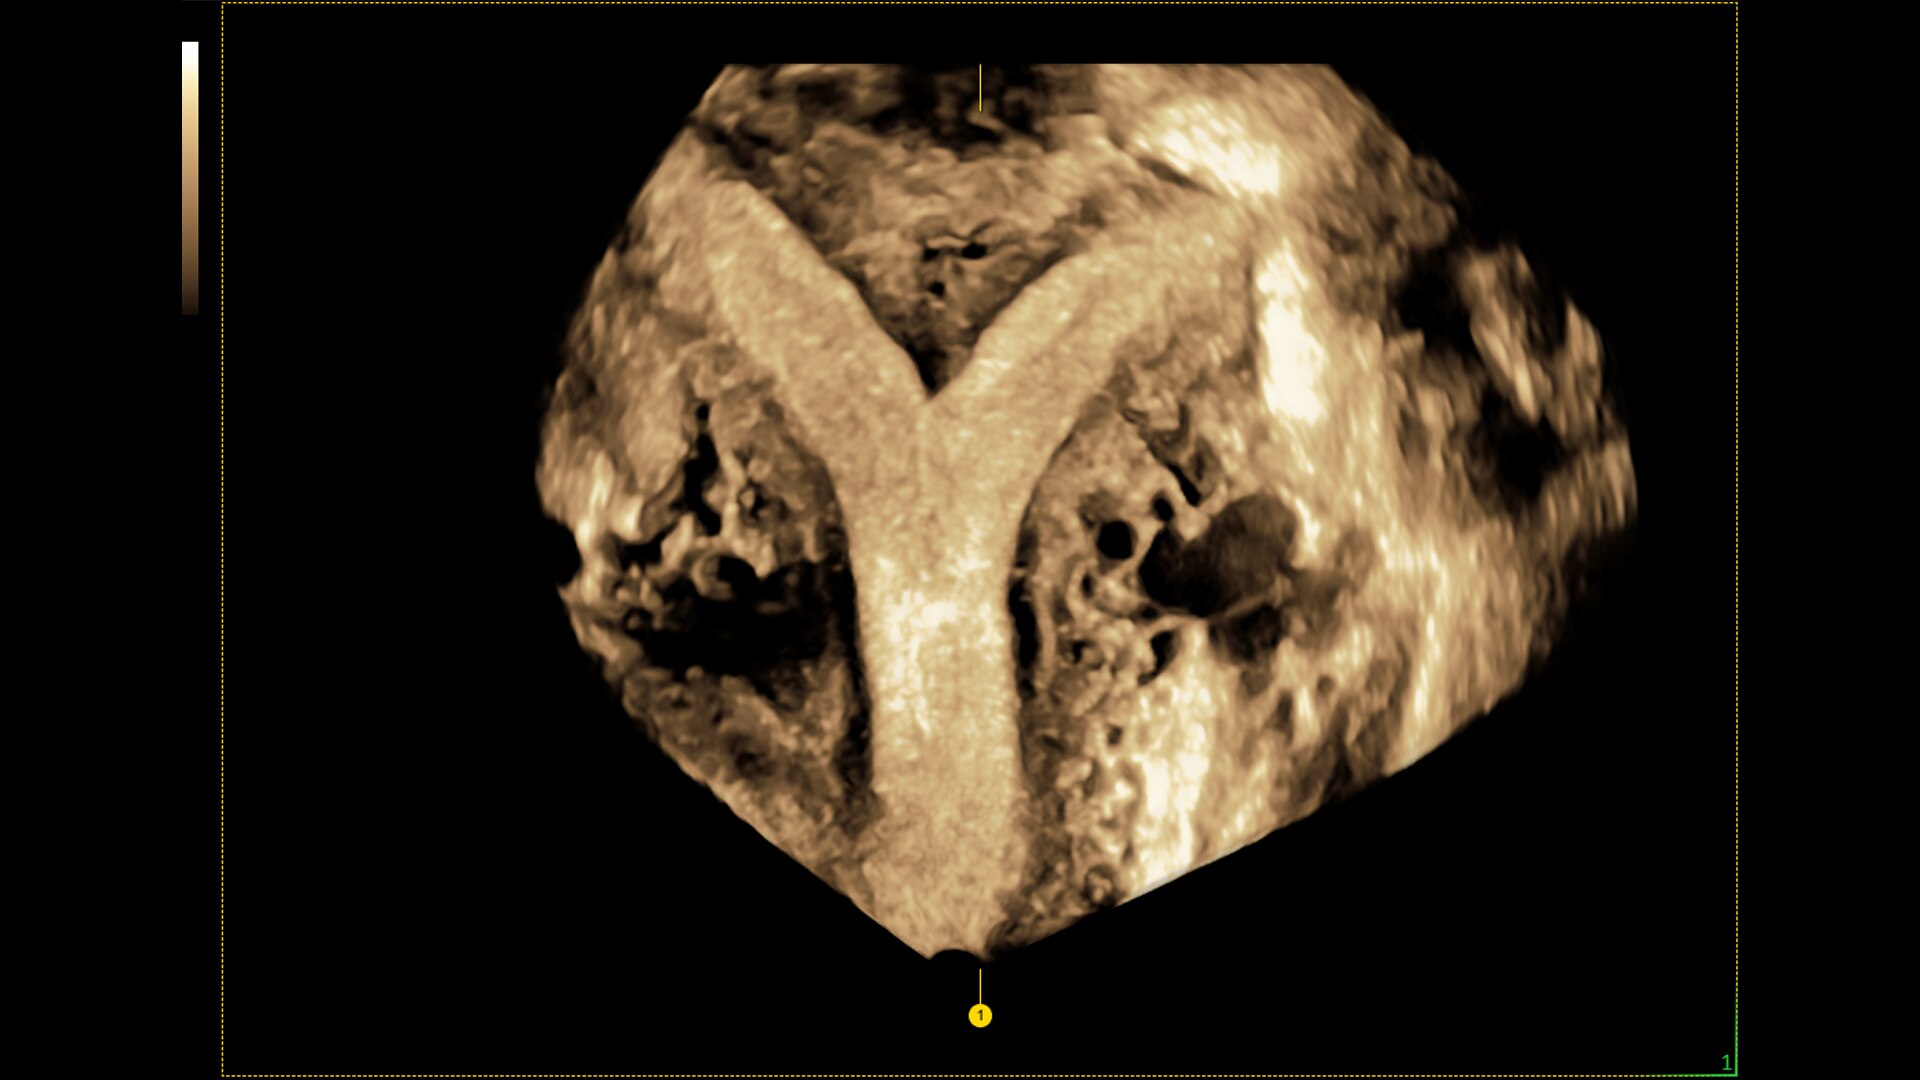

Fast, easy 3D-like blood flow visualization

Next level color Doppler that delivers exceptional sensitivity for easy, fast visualization of blood flow, displaying a 3D like appearance as seen in this 27-week fetal heart.